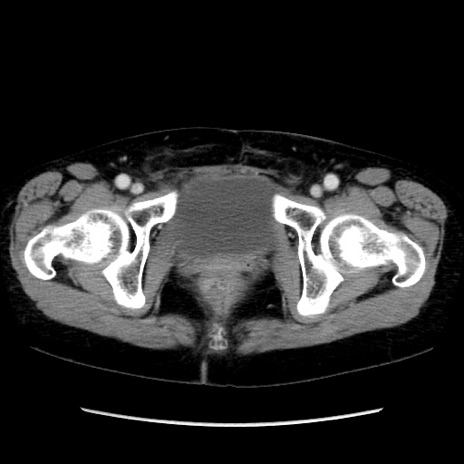

症例32(横断像)

【症例】40歳代 女性

【主訴】上腹部痛、嘔気・嘔吐

【現病歴】約9時間前頃から急に上腹部痛、嘔気、嘔吐が出現。改善しないため救急要請。

【既往歴】子宮頚癌(広汎子宮全摘術、放射線療法)、腸閉塞

【身体所見】腹部:平坦、軟、腸雑音亢進、上腹部を中心に腹部全体に圧痛あり。

【データ】WBC 8400、CRP 0.03